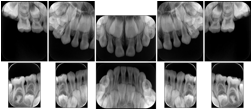

Intra-oral radiography typically involves acquisition of multiple images of various parts of the dentition. Many digital radiographic systems offer customized templates that are used for displaying the images in a study on the screen. These templates may also be referred to as mounts or view sets. The Structured Display Object represents a standard method of encoding and exchanging the layout and intended display of Structured Displays. A structured display object created in this manner could be stored with a study and exchanged with images to allow for complete reproduction of the original exam.

1. A patient visits a General Dentist where a Full Mouth Series Exam with 18 images is acquired. The dentist observes severe bone loss and refers the patient to a Periodontist. The 18 images from the Full Mouth Series along with a Structured Display are copied to a DICOM Interchange CD and sent with the patient to see the specialist. The Periodontist uses the CD to open the exam in his Dental Radiographic Software and consults via phone with the General Dentist. Both are able to observe the same exam showing the images on each user's display using the exact same layout.

Intra-oral Full Mouth Series Structured Display

Figure OO-1. Intra-oral Full Mouth Series Structured Display